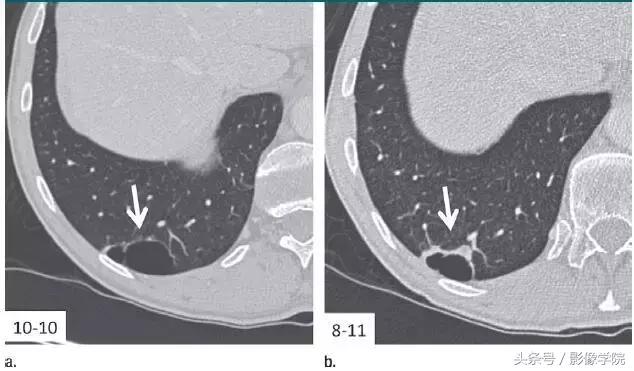

7、相隔10个月的囊肿渐进表现

图 7 相隔 10 个月后进行的层厚 1 mm CT 横断面图像,显示右肺下叶囊肿壁渐进增厚的高度可疑模式(箭头)。手术证实为浸润性腺癌。